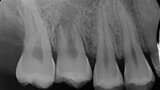

Fig. 16a: Pre-op periapical radiograph.